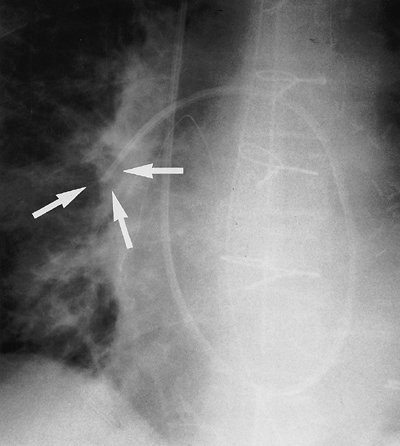

Pleural drainage tubes are used for evacuation of pleural fluid and air (hydrothorax and pneumothorax, respectively). Several types and sizes of tubes are used, and all should be evaluated by chest radiography for proper placement of the tip and side holes. A side hole is marked by an interruption of the radiopaque identification line; it should be medial to the inner margin of the ribs (Fig. 5-27). Placement of the tube tip in the

P.75

subcutaneous tissues, a fissure, or the lung parenchyma can be diagnosed with chest radiography or CT scanning. CT scans can also be used to identify loculated pleural collections and direct the placement of drainage tubes. Location within a fissure can be suspected when the tube reproduces the anatomy of the minor or major fissure, or when the tube takes more of a horizontal rather than a vertical course as seen on a frontal chest radiograph. Tubes within fissures may become occluded by the surrounding lung. Tubes can be inadvertently advanced into the mediastinum or through the lung parenchyma, liver, spleen, or diaphragm, resulting in bronchopleural fistula, hemorrhage, and infection (20,30). After removal of a thoracostomy tube, a residual pleural or parenchymal line from the tube track is often identified on the chest radiograph (Fig. 5-28); this should not be mistaken for the visceral pleural edge of a pneumothorax. If a large amount of pleural fluid is removed at one time (e.g., >1.5 L), rapid lung re-expansion can, rarely, result in so-called "re-expansion" pulmonary edema.